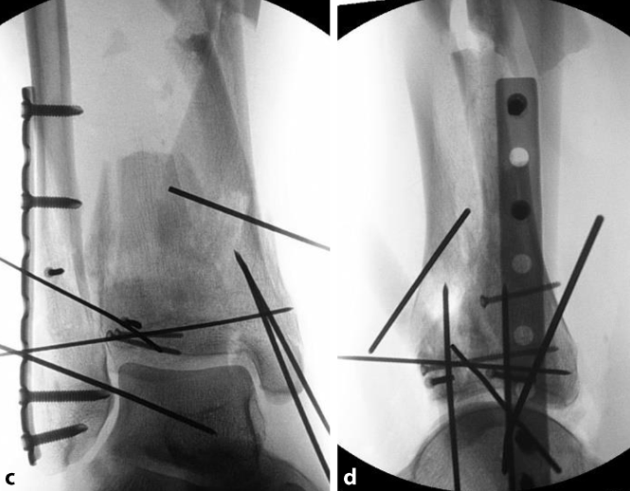

图a、b. 术前X线片显示Pilon骨折(AO 43-C3)。由于干骺端存在粉碎区域,关节骨折块与完整的骨干之间缺乏参照;c、d. 通过 “扩大外侧入路” 联合小的内侧入路,首先对关节骨块进行解剖复位,从而将C型骨折转化为A型骨折。随后,对骨折进行功能对位并固定到骨干上。